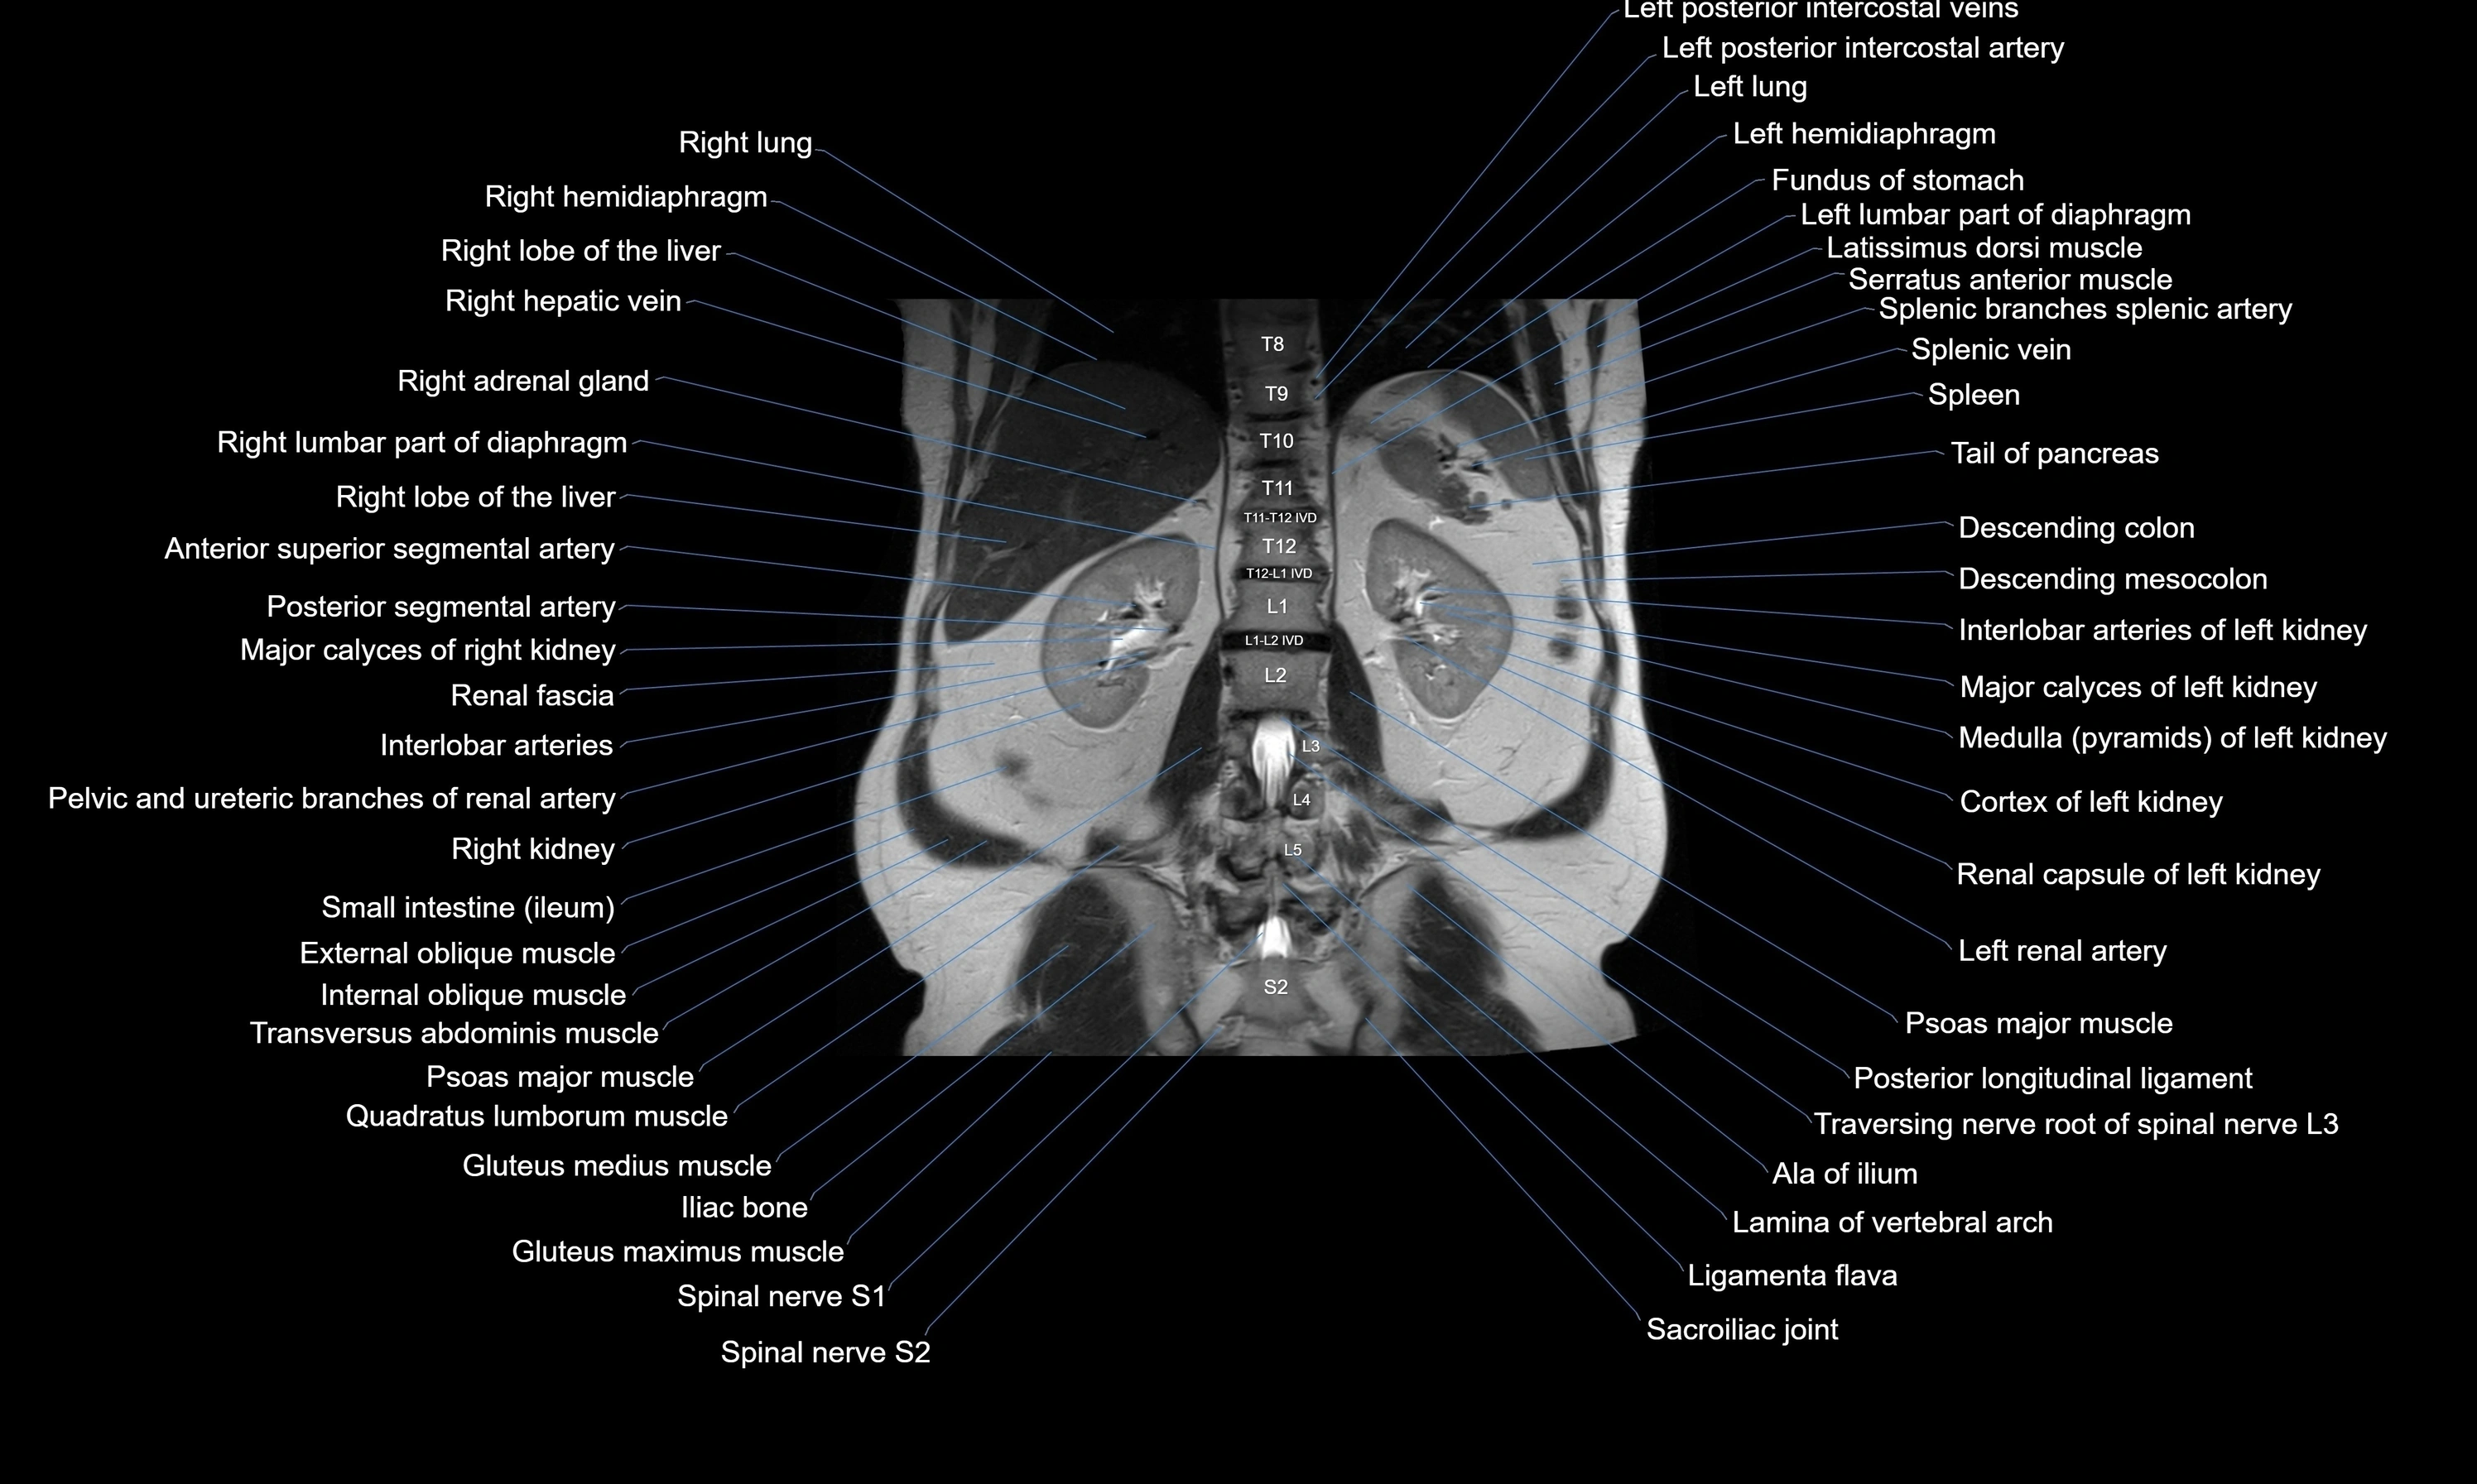

- Descending colon

- Descending mesocolon

- Left kidney

- Left renal artery

- Psoas major muscle

- Quadratus lumborum muscle

- Right kidney

- Right lobe of liver

- Spleen

- Tail of pancreas